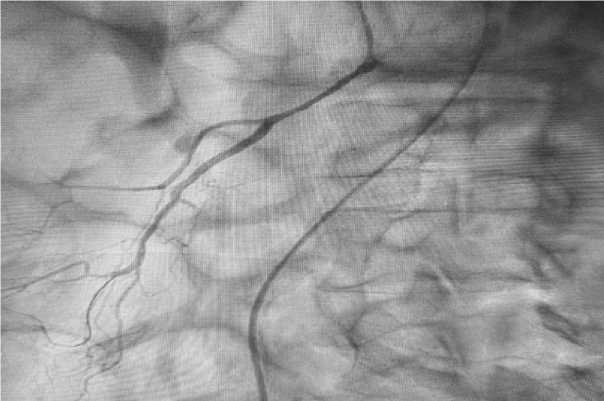

Хирургическое лечение. 01.07.2023 в 20.00. под местной анестезией выполнена катетеризация ВБА трансфеморальным артериальным доступом по Сельдингеру. При селективной ангиографии выявлен тотальный тромбоз верхней брыжеечной артерии дистальнее устья (рис. 1). За зону тромбоза в подвздошно-ободочную артерию проведен тромбоаспиратор. С учетом большого диаметра ВБА и массивного тромбоза тромбоас-пирация через коронарный аспирационный катетер была малоэффективной. Принято решение провести тромбоаспирацию через проводниковый катетер JR 4.06F. Для снижения риска диссекции артерии была сформирована двуоксиальная система «проводниковый катетер – аспирационный катетер», которая по проводнику проведена до дистального отдела подвздошнокишечной артерии. Получено большое количество тромботических масс. На контрольной ангиографии выявлено, что антеградный кровоток восстановлен, однако имеется множество пристеночных тромбов, а также тромбоз основного ствола кишечных артерий и подвздошно-кишечной артерии. С учетом массивного тромбоза и высокой вероятности повторного тромбообразования в ветвях ВБА принято решение о суперселективном введении раствора «Тирофабана» (ингибитора гликопротеинов Iib/IIIa-рецепторов) через дозатор по схеме. Крупные тромбы в основном стволе подвздошно-кишечной артерии были фрагментированы посредством баллонной ангиопластики и на активной аспирации удалены. На контрольной ангиографии ВБА выявлено, что антеградный кровоток по основным ветвям восстановлен, местами имеются пристеночные тромбы, не влияющие на скорость кровотока (рис. 2). За время оперативного вмешательства пациент получил 10 000 ЕД гепарина.

Рис. 1. Ангиография пациента при поступлении с острым мезентериальным тромбозом